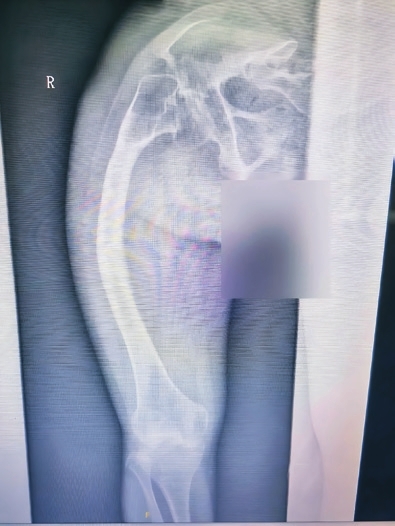

原来,张女士从小就患上了一种怪病,这导致她本身的骨头质量很差,骨头的强度也不够,右侧大腿严重向外弯曲。祸不单行的是,2021年,张女士不慎发生了车祸,她的右侧大腿股骨干被撞骨折。当时张女士采用了传统钢板内固定方法进行治疗。随着时间的推移,张女士骨头逐渐痊愈。谁料就在今年2月,张女士又再次发生车祸,仍然是右侧大腿股骨发生了骨折,这使得张女士被迫再次接受手术,腿骨又一次用钢板固定起来。经过一段时间的休养,张女士重新恢复了自主行走。然而,今年7月,命运似乎又和张女士开起了玩笑。有一天,张女士在家不经意地从座椅上站起时,只听见“嘎巴”